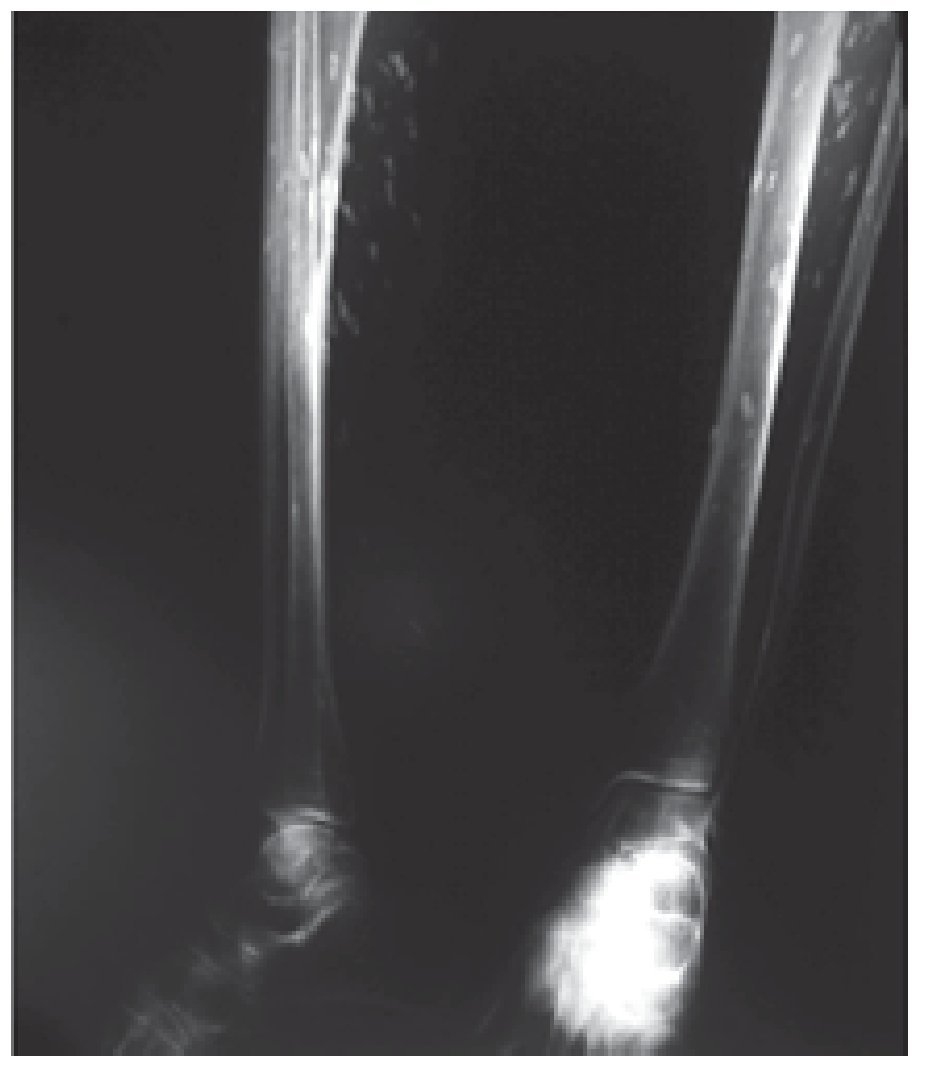

Mujer de 88 años, procedente de Zacatecas, enviada por diarrea, flatulencia y dolor cólico abdominal intermitentes, con duración de uno a dos días por semana, asociados claramente con la ingesta de productos lácteos. Refirió también polimialgia difusa y continua, todo con más de 10 años de evolución. Nunca antes había acudido con un médico por esta sintomatología. La paciente solía elaborar productos cárnicos que consumían en casa y uno de sus hijos fue operado de cisticercosis cerebral. Contaba con una radiografía simple de abdomen (Figura 1). Al ver la imagen radiográfica y correlacionarla con las polimialgias, se solicitaron radiografías de tórax y miembro pélvico (Figuras 2-4), reacción a la cisticercosis (ELISA) con resultado negativo, y dos biopsias del músculo donde habían calcificaciones. El informe de patología señaló nódulo encapsulado con calcificación difusa, compatible con parasitosis, cuya calcificación del contenido dificulta determinar el tipo de parásito; músculo esquelético con cambios reactivos y tejido fibro-conectivo y adiposo con arterioesclerosis de Möckenberg.

¿ Figura 3. Ambas piernas con el mismo tipo de calcificaciones.

Existe poca información sobre la cisticercosis diseminada, pero se considera una entidad rara. La reacción a la cisticercosis resulta negativa en estos casos, debido a que no hay parásitos vivos y las polimialgias se deben a reacción inflamatoria en respuesta a las calcificaciones. La información sobre miopatía o miositis por cisticercosis muscular diseminada es muy escasa, pero al tratarse de una infección inactiva, el tratamiento es sólo sintomático con base en antiinflamatorios no esteroideos o analgésicos de acuerdo a los requerimientos del enfermo.